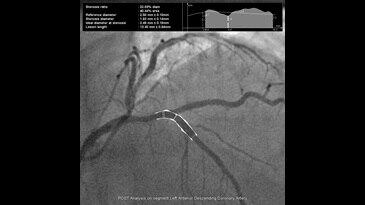

- InnovaSpin — оптимальная проекция сосуда за одну инъекцию контраста. Клиническое приложение для ротационной ангиографии Innova Spin позволяет увидеть всю камеру сердца и анатомию коронарных сосудов за одну съемку и с одной инъекцией контраста;

- Innova 3D — получение трехмерных изображений в операционной. Программное обеспечение трехмерной ангиографии Innova 3D — это режим получения трехмерных изображений из ротационной ангиографии, предоставляющий точную сосудистую визуализацию, непосредственно у операционного стола. Приложение позволяет получить трехмерную реконструкцию с высоким пространственным разрешением путем измерения спектра плотностей окружающих тканей;